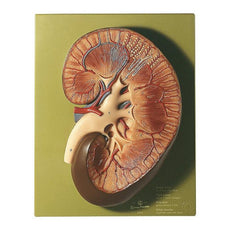

One front half of a kidney is removable from the anatomical model of the urinary system. With easy to change male insert (bladder and prostate, front and rear half) and female insert (bladder, womb and ovaries, 2 lateral halves) the Urinary System model is a great teaching tool.